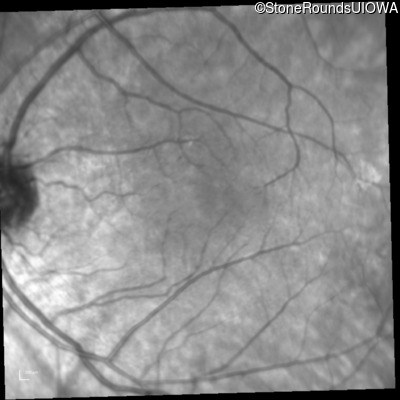

Infrared Fundus Photograph - Right - 20/25

Exemplar